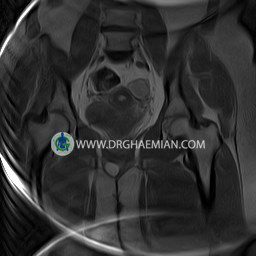

پزشکان اغلب از تصویربرداری ام آر آی برای تشخیص و درمان عارضه های پزشکی که فقط با استفاده از اشعه ایکس یا میدان مغناطیسی و امواج رادیویی قابل مشاهده است، استفاده می کنند. دستگاه ام آر آی تصاویر دقیق از ساختار های داخلی بدن ایجاد می کند. در این کیس کیست بارتولین لگن و تجمع دورمقعدی و کیست ساده ایی در تخمک چپی دیده می شود.

HIP JOINT MRI

( without contrast )

Technique : coronal STIR , coronal T2 , Axial T1 , axial T2 .

REPORT:

The femoral heads and acetabula are normal shape , signal intensity and the femoral heads are well covered by the acetabular margins .

The joint spaces are of normal width without fluid collection .

the articuler surfaces are smooth and congruent and show normal cortical thickness .

there are no marginal osteophytes or subchondral signal changes .

The bone marrow shows normal signal intensity , especially in the femoral head and neck .

Each femoral shaft has normal margins and contains a normal bone marrow signal .

– Simple cyst (28×32mm) in left ovary

– Cyst like lesion (20×25mm) in right vaginal wall suggestive for bartholin cyst and perianal collection

are seen.

COMMENT: Clinical correlation is recommended.